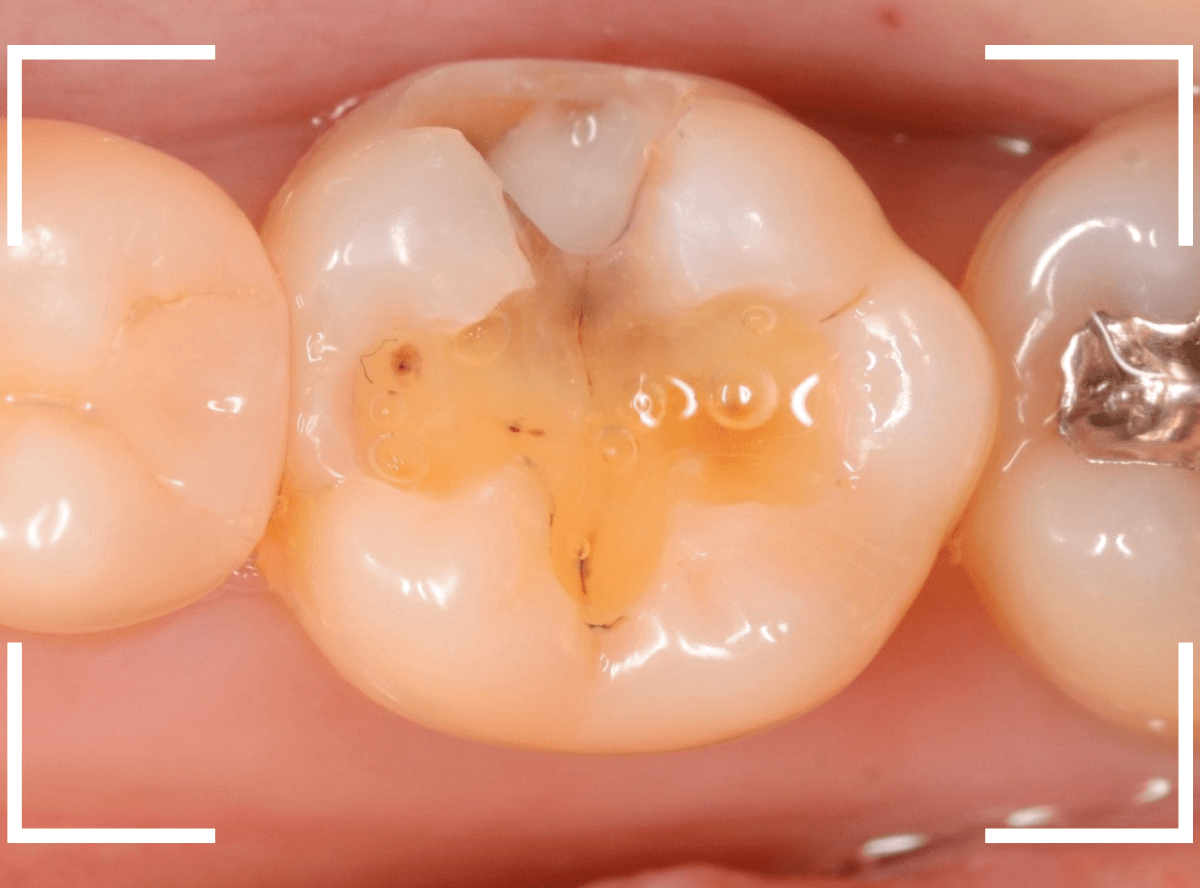

まずは、麻酔をしてつめ物を慎重に外してみます。

両歯とも、色々嫌な予感のする所見です。

レジンを除去して虫歯を調べます。

赤い部分が虫歯です。

少しずつ虫歯が出てきました。